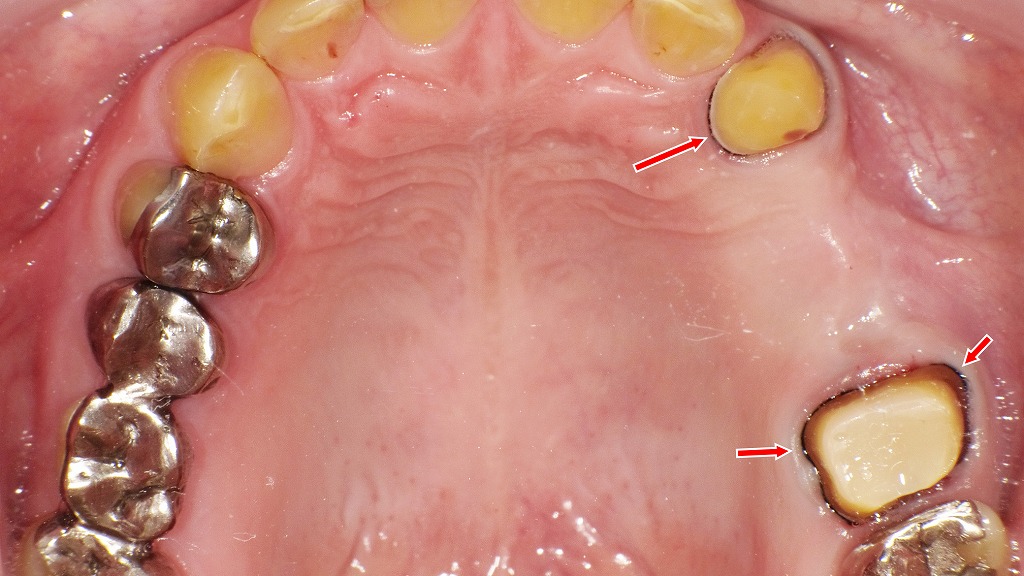

この写真は、上顎の口蓋側から撮影された口腔内写真です。

🦷 全体の状況

上顎右側犬歯(3番)から右上第1大臼歯(6番)にかけてのブリッジ形成後の状態です。歯列の中央やや右側に見える赤い矢印部分には、印象採得(型取り)のために歯肉圧排糸が挿入されています。歯肉縁下のマージン(支台歯の境界線)を明確にする目的です。

🔹 上顎3番(犬歯)

- 生活歯(歯髄が生きている)であり、削合量が比較的少なく保たれています。

- 歯肉縁に沿って細い圧排糸が見られ、出血や腫脹はなく、適切に圧排されています。

- 今後、ブリッジの支台歯としてメタルボンド冠が装着される予定。

🔹 上顎6番(第1大臼歯)

- ファイバーコア(グラスファイバー強化樹脂製のコア)が築造されています。

- コア表面は滑沢で、支台歯形成のラインが明瞭。

- 歯肉縁には圧排糸が挿入され、マージンがしっかり露出しています。

- 周囲歯肉に炎症所見はなく、印象採得に適した状態。

🔹 他の歯の状態

- 左上の臼歯部には銀合金インレー・クラウンが装着されています。

- 口蓋粘膜は健康的な淡紅色を呈し、腫脹や潰瘍などの異常所見はありません。